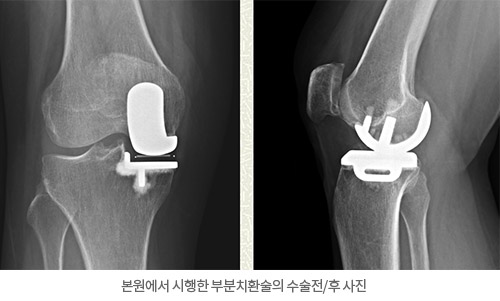

본원에서 시행한 부분치환술의 수술전/후 사진

의료용 톱을 이용하여 손상이 있는 연골을 절제하고 금속 보형물로 경골과 대퇴골의 관절면을 교체하게 됩니다. 금속 고형물들은 뼈를 골 시멘트로 고정하게 되며 플라스틱 보충물을 위 아래 금속 보형물 사이로 삽입하게 되어 대퇴 금속 보형물과 경골 금속 보형물과의 움직임을 부드럽게 합니다.